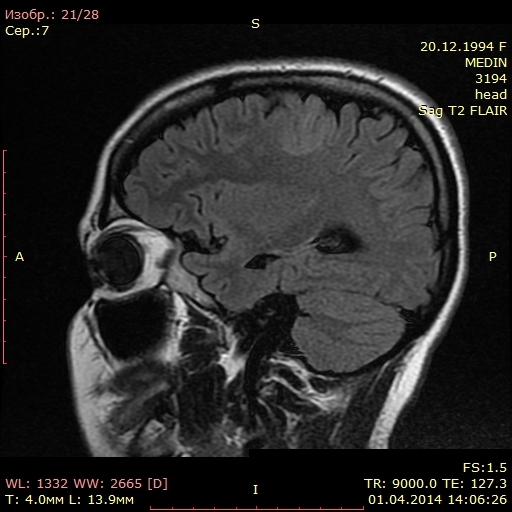

Мрт головного мозга мосто мозжечкового угла